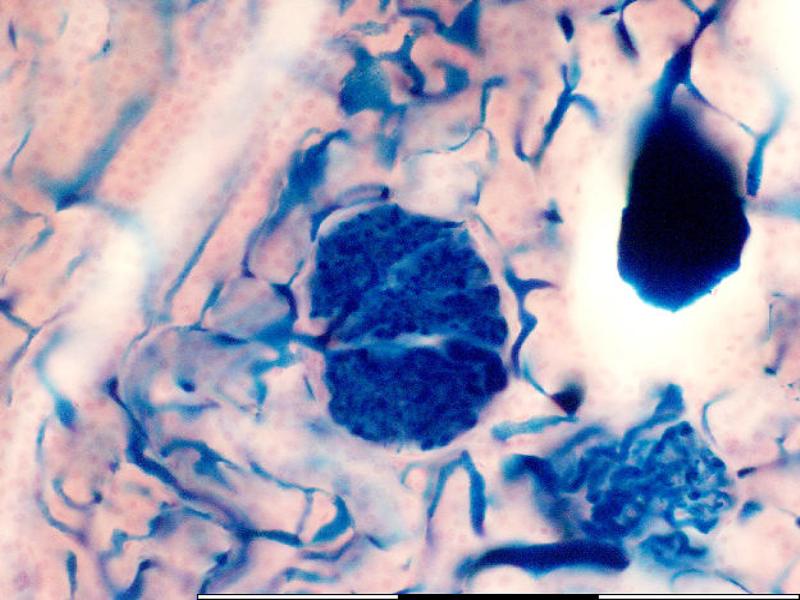

What can you identify on the next slide?

Make a list before advancing.

Cuboidal epithelium is associated with ducts. The kidney consists of ducts, most of which are lined with cuboidal epithelium.